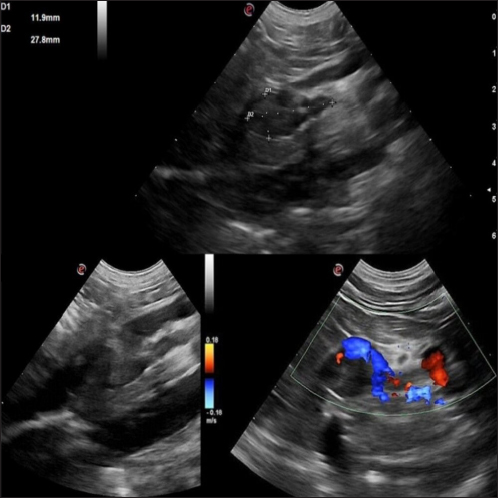

The abdominal ultrasound examination (Fig. 2) revealed an abnormal right adrenal gland with the presence of a not-occluding structure in the lumen of the CVC. The right adrenal gland cranial pole appeared to increase in volume (12 × 25 mm), with a mixed echogenicity, dishomogeneity, and an irregular profile with the invasion of the CVC. At color Doppler, a reduced residual flow was documented at that site in CVC.

Fig. 2. Right adrenal gland showed an irregular profile and dishomogeneity and the CVC was invaded by a mass not completely occluding the vassel. A residual flow is visible with color Doppler through the vessel.

In our case, ultrasound was a basic and immediate means to address to the final diagnosis documenting an adrenal mass invading the CVC. Furthermore, a severe hypertensive cardiopathy was documented at echocolordoppler further supporting the suspected diagnosis. In our case, contrast-enhanced ultrasound (CEUS) and/or fine needle aspiration (FNA) sampling were not performed. Due to the presence of caval invasion, malignancy was immediately suspected, and a CT evaluation was preferred. Once the CVC invasion was also confirmed by CT, a surgical approach was planned.